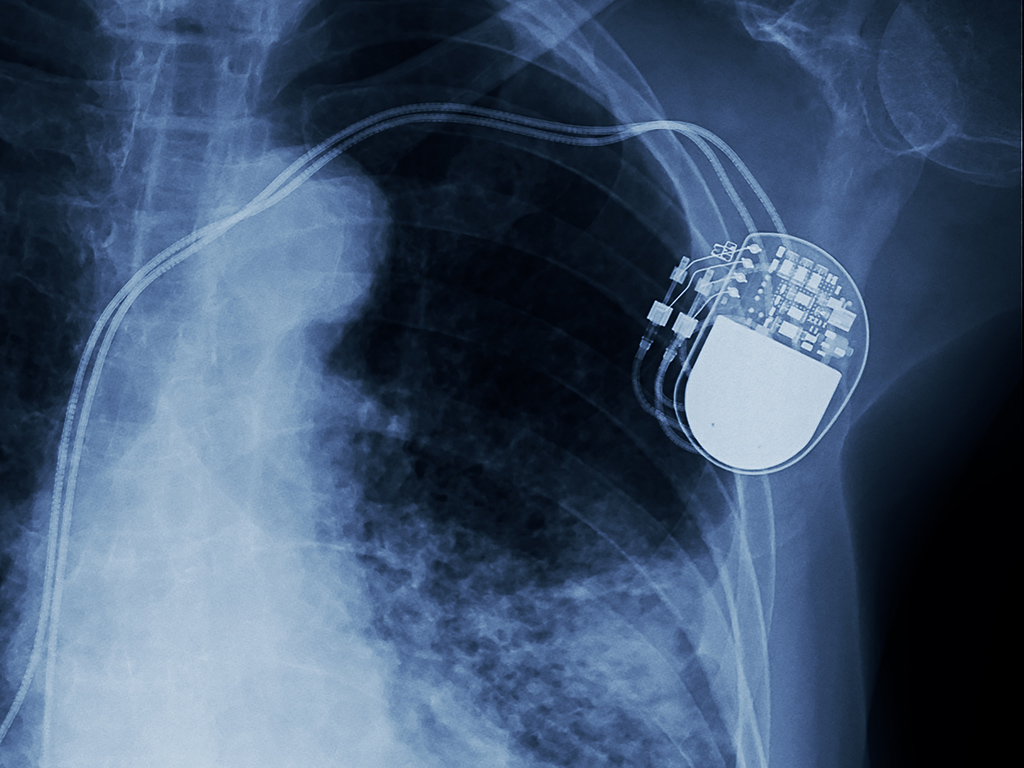

Кардиостимулятор - это специальный прибор, который с помощью электрических импульсов задает сердцу правильный ритм и тем самым спасает от жизнеугрожающих состояний. Кардиостимулятор состоит из 2 частей: металлического корпуса, включающего специальную микросхему, батарейку и электродов. Средний срок службы от 7 до 10 лет.

Операция является малотравматичной и относительно безопасной. Занимает от 40 минут до 2 часов (в зависимости от вида стимулятора). Операция проходит под местной анестезией: раствором новокаина или лидокаина обкалывают подключичную область (чаще слева). Делается разрез длиной до 5 см ниже ключицы. Под кожей формируется карман (ложе), в котором будет находится корпус стимулятора. Через подключичную вену электрод заводится в полость правого предсердия или желудочка при однокамерном, в полость правого предсердия и желудочка при двухкамерном стимуляторе. Существуют несколько видов электродов:

Затем, хирург находит наиболее чувствительное место для стимуляции. Электроды фиксируются и подсоединяются к корпусу стимулятора. Рана послойно ушивается.